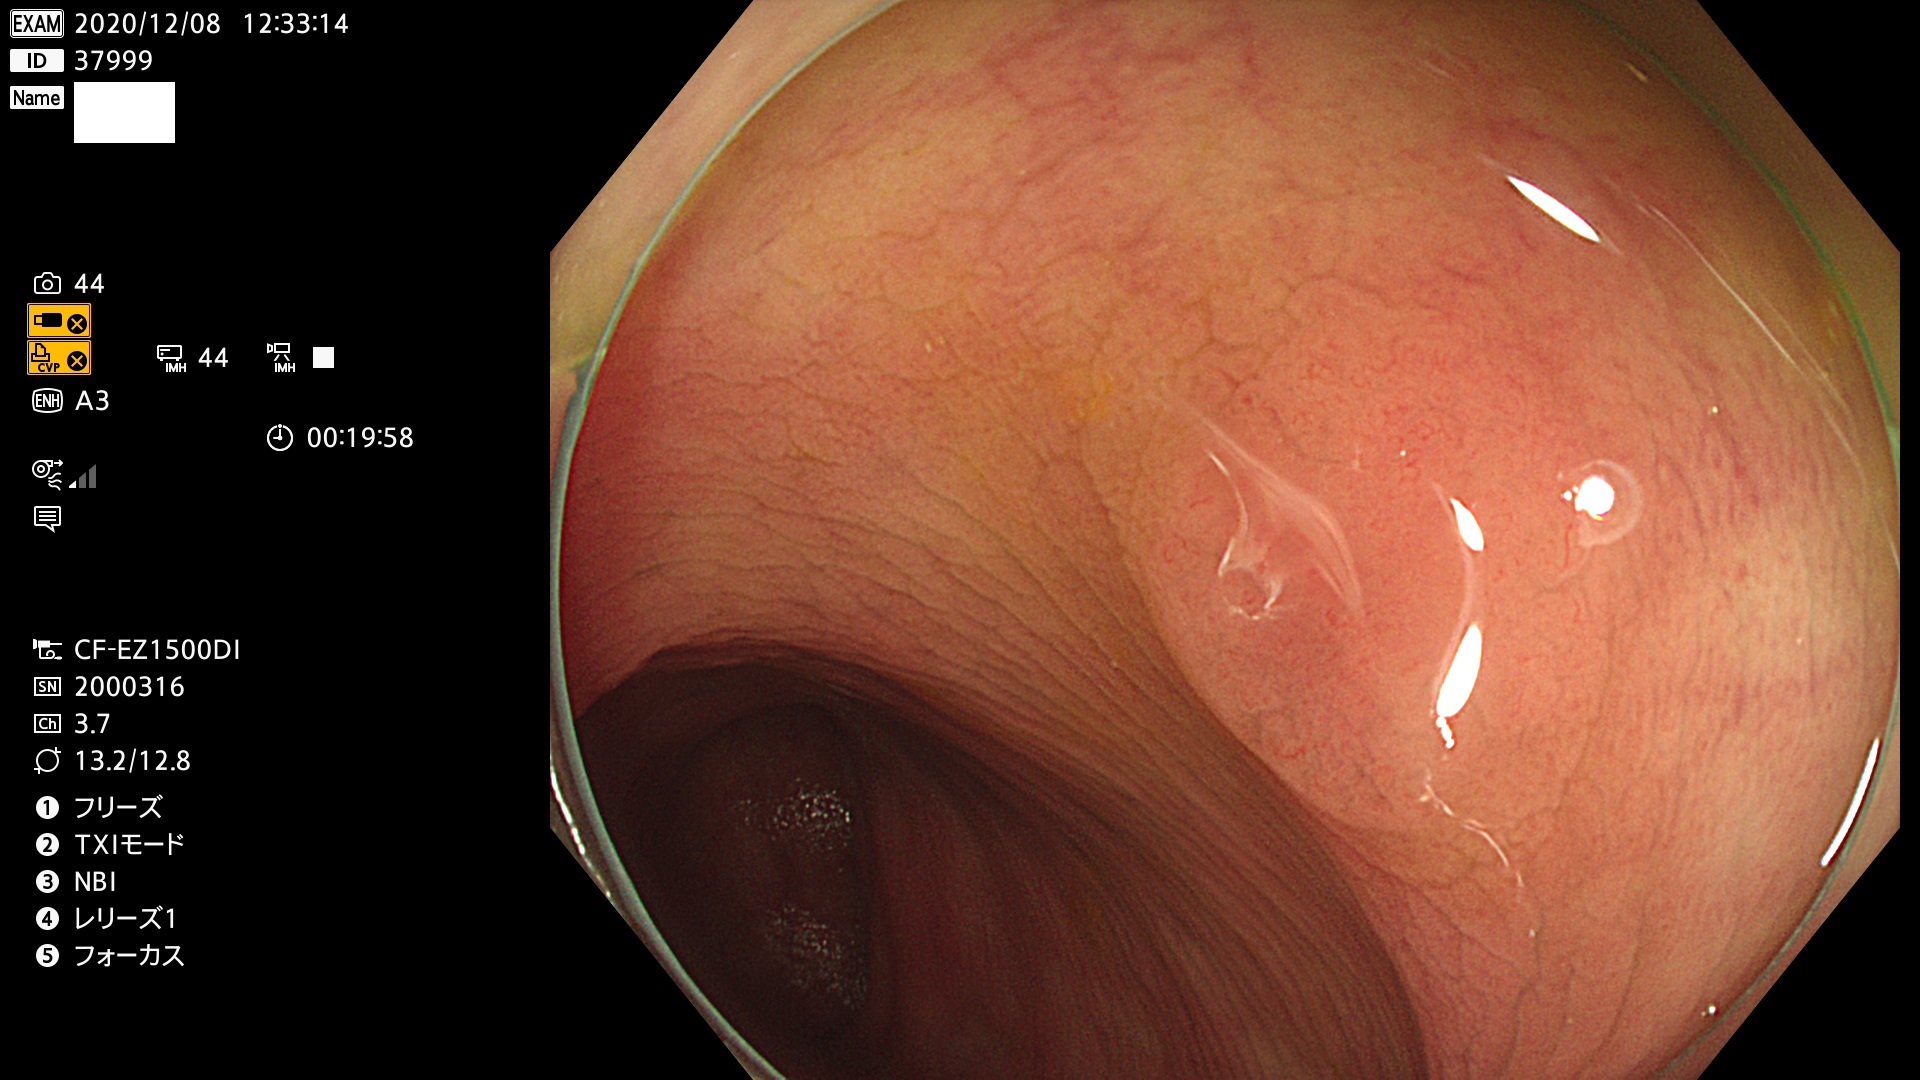

腺腫発見率 78  % (カルテ番号 37900〜37999の100名の方の検査結果で集計)

37900 37902 37903 37904 37905 37906 37907 37909 37910 37911 37912 37913 37914 37915 37916 37917 37919 37921 37922 37923 37926 37928 37929 37930 37931 37933 37934 37935 37936 37937 37938(SSAPのみ) 37939 37940 37941 37942 37943 37946 37947 37948 37949 37951 37952 37953(SSAPのみ) 37955 37956 37957(SSAPのみ) 37958(SSAPのみ) 37960 37962 37963 37964 37966 37967 37968 37971 37972 37973 37975 37976 37977 37979 37982 37983 37984 37985 37986 37987 37988 37989 37990 37991 37992 37993 37994 37995 37996 37998 37999